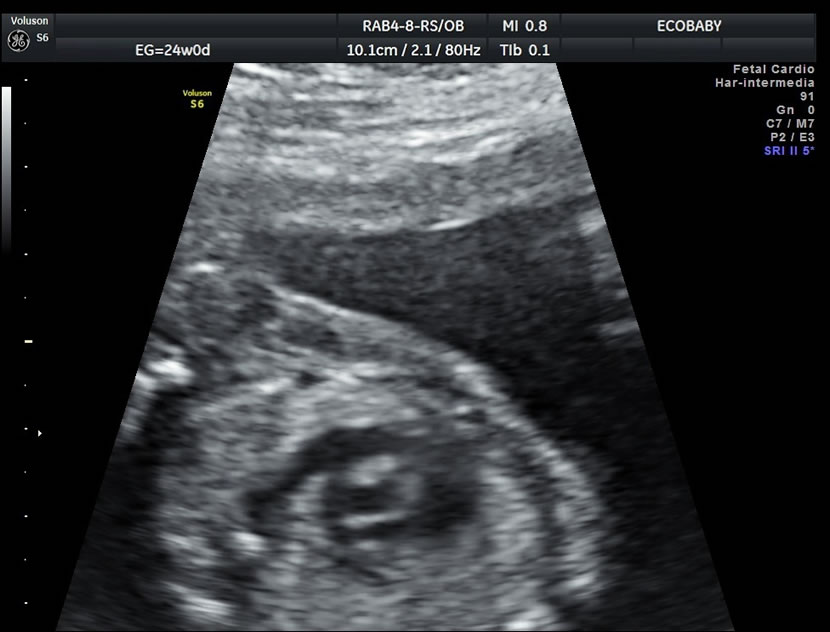

Cerebro, cuello, cara, tórax, corazón (diferentes cortes que muestran las cavidades y la correcta entrada y salida de arterias y venas), abdomen (normalidad de la pared, estómago, intestino, riñones, vejiga), miembros inferiores y superiores y columna vertebral.